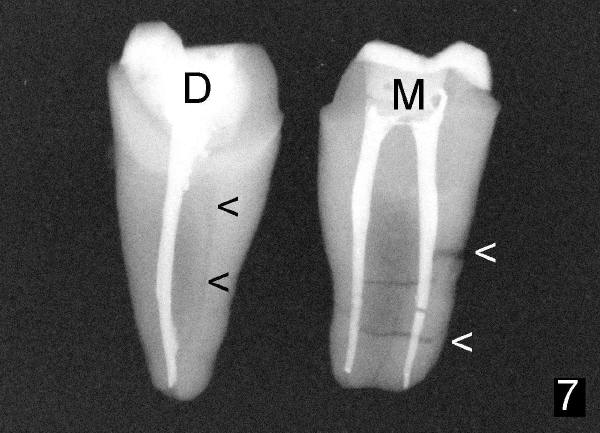

Let us return to Fig.5, turn the mesial portion of the tooth 180 degree as shown by a curved arrow and take PA (poor man CT, Fig. 7). Missing DB canal (black <) and mesial root fracture (white <) are further confirmed. Further question: why is the missing canal not the reason for failure of this tooth?